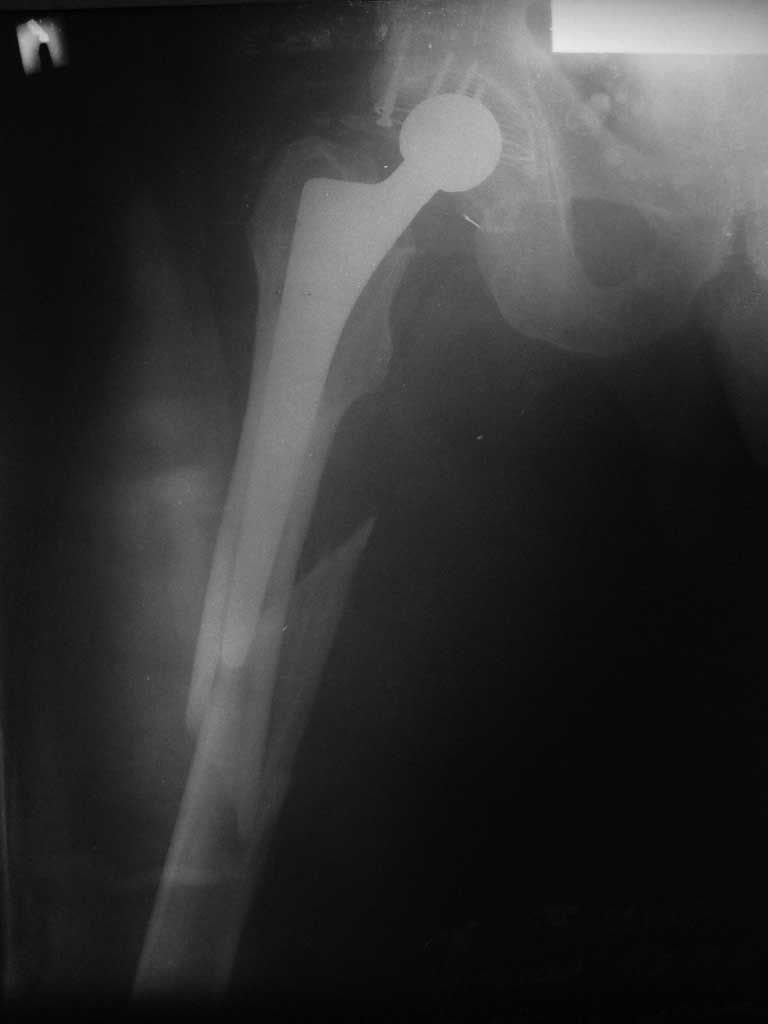

Делает их ФГУП "ЦИТО", Москва. А где пациент находится? Таких операций не очень много, мы стараемся каждую задокументировать. Может, получится поучаствовать кому-то из нас... Покажите pls снимки, что за перелом, какой протез.

Пациенту 72 года, оперировался 11 лет назад в ГКБ15 Москва. Судя по снимку ножка споторно фирмы матис. Вряд ли сможем найти такую же для примерки.

Дополнительные снимки